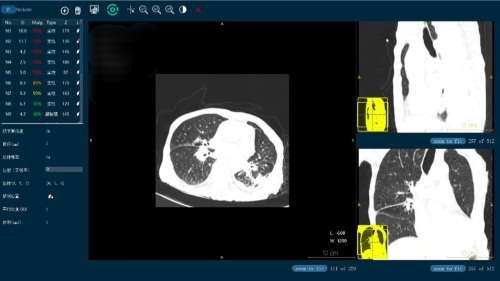

在放射領(lǐng)域,其研發(fā)的肺部CT智能輔助診斷系統(tǒng)Lung-Sight能夠自動檢測病人的結(jié)節(jié)病灶部位并做出定量測算。3-30毫米的結(jié)節(jié)敏感度可達95%以上,且假陽性控制在2個以下;尤其對于3-5mm的微小結(jié)節(jié)檢測,能大大降低醫(yī)生的閱片時間,同時減少漏診誤診情況。DR-Sight(胸片智能輔助篩查)產(chǎn)品能夠?qū)π男夭课贿M行多達十余種病癥的辨識,可廣泛應(yīng)用于體檢部門和住院門診,協(xié)助醫(yī)生迅速篩檢病癥、標識病變位置,并自動生成圖文報告。此項產(chǎn)品已遞交CFDA申請,現(xiàn)已進入臨床試驗階段。

微信圖片_20180331092401.jpg

(圖為視見科技的影像產(chǎn)品)